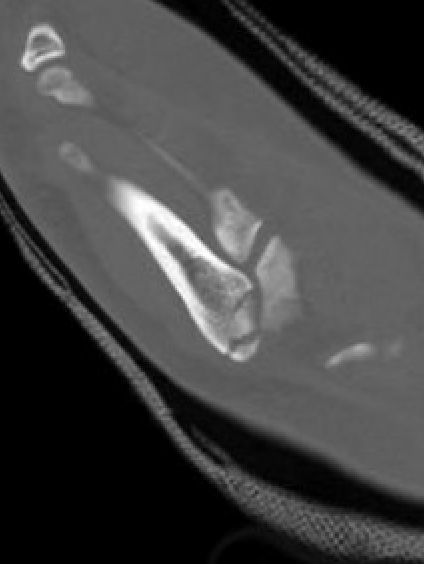

Xray

Zone 3 Fractures

Progression to nonunion of zone 3 fracture with nonoperative care

Torg Classification

| Type I | Type II | Type III |

|---|---|---|

| Acute | Delayed union | Nonunion |

|

Narrow fracture line No sclerosis No cortical reaction No periosteal hypertrophy |

Increased fracture line Both cortices Some sclerosis Some periosteal hypertrophy |

Significant sclerosis Significant cortical hypertrophy |